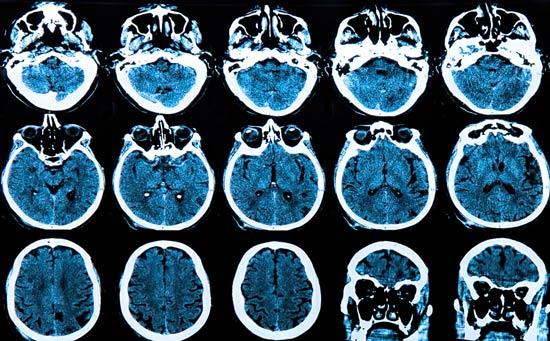

Derrame cerebral: ¿Pueden presentarse en los niños?

El derrame cerebral es poco frecuente entre los niños y bebés, pero puede ocurrir.

Un accidente cerebrovascular es la interrupción del flujo de sangre hacia el cerebro.

Las células del cerebro en el área circunvecina mueren de inmediata y las que están en las áreas circundantes se ven afectados por la reducción del flujo sanguíneo.

Una vez las células cerebrales mueren, también mueren sus funciones.